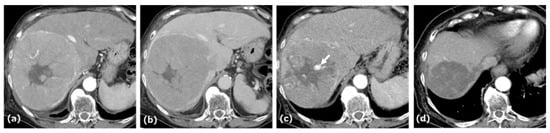

A woman in her seventies was referred to our hospital for evaluation of a hepatic mass, incidentally detected by ultrasonography during a workup for abnormal liver enzymes. She had a history of daily alcohol consumption (approximately 700 mL per day for 30 years). Laboratory data and tumor markers were as follows: aspartate aminotransferase (AST): 101 U/L, alanine aminotransferase (ALT): 627 U/L, lactate dehydrogenase (LDH): 235 U/L, alkaline phosphatase (ALP): 164 U/L, gamma-glutamyl transpeptidase (γ-GTP): 154 U/L, total bilirubin: 0.9 mg/dL, α-fetoprotein (AFP): 85.5 ng/mL, protein induced by vitamin K absence or antagonist-II (PIVKA-II): 30,056 mAU/mL, and carcinoembryonic antigen (CEA): 7.0 ng/mL. Serological testing for hepatitis B virus revealed negative results for HBV DNA. Anti-HBs was 14.7 mIU/mL, whereas anti-HBc was 0.35 S/CO. Contrast enhanced CT (CE-CT) demonstrated an approximately 10.3 cm tumor in the anterior segment of the liver, showing arterial-phase enhancement with a pseudocapsule, followed by washout on the portal and delayed phases (Figure 1).

Figure 1. CE-CT of Case 1. CE-CT showed a large HCC in the anterior segment of the liver with arterial-phase hyperenhancement (a) and portal-phase washout with a surrounding pseudocapsule (b). After four cycles of AB therapy, arterial-phase CT demonstrated a vascular lake-like phenomenon ((c), arrow). On arterial-phase CT obtained after a total of seven cycles of AB therapy, tumor regression was observed (d). Locoregional therapy (conventional transarterial chemoembolization (cTACE) followed by radiofrequency ablation (RFA)) was subsequently performed with curative intent (e).

This patient was diagnosed with uHCC. The Child–Pugh score was 5. AB therapy was selected as the first-line treatment for this patient. After four cycles of this combination therapy, tumor size decreased from 10.3 cm to 9.4 cm, and treatment response was categorized as stable disease (SD) according to Response Evaluation Criteria in Solid Tumors (RECIST) 1.1. At this time, patchy pooling of contrast medium within the tumor was observed. After seven cycles of this therapy, the tumor size was reduced to 4.3 cm, and the response was categorized as a partial response (PR) based on RECIST 1.1. After eleven cycles of this therapy, the patient underwent cTACE followed by RFA with curative intent, after which AB therapy resumed and continued to a total of 22 cycles.